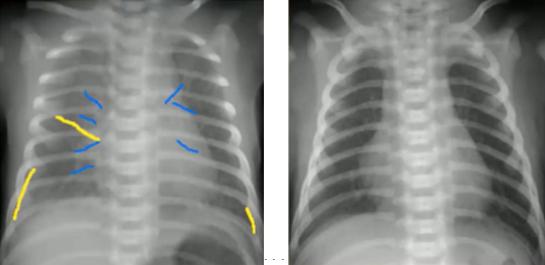

为了避免在胸片阅读中出现错误和遗漏,可根据以下ABCDE的步骤来记忆胸片的阅读顺序:

1、Airway/气管及主支气管(蓝色):是否居中、对称,有无左右偏移;

2、Breathing/肺及胸膜(绿色):胸膜有无增厚或阴影;

3、Circulation/心脏及纵隔(红色):心脏位置、大小、密度;纵隔位置、密度、面积;

4、Disability/骨头(黄色):有无骨折;

5、Everything else:气管插管、气胸、异物等。

图4.胸片阅读Checklist